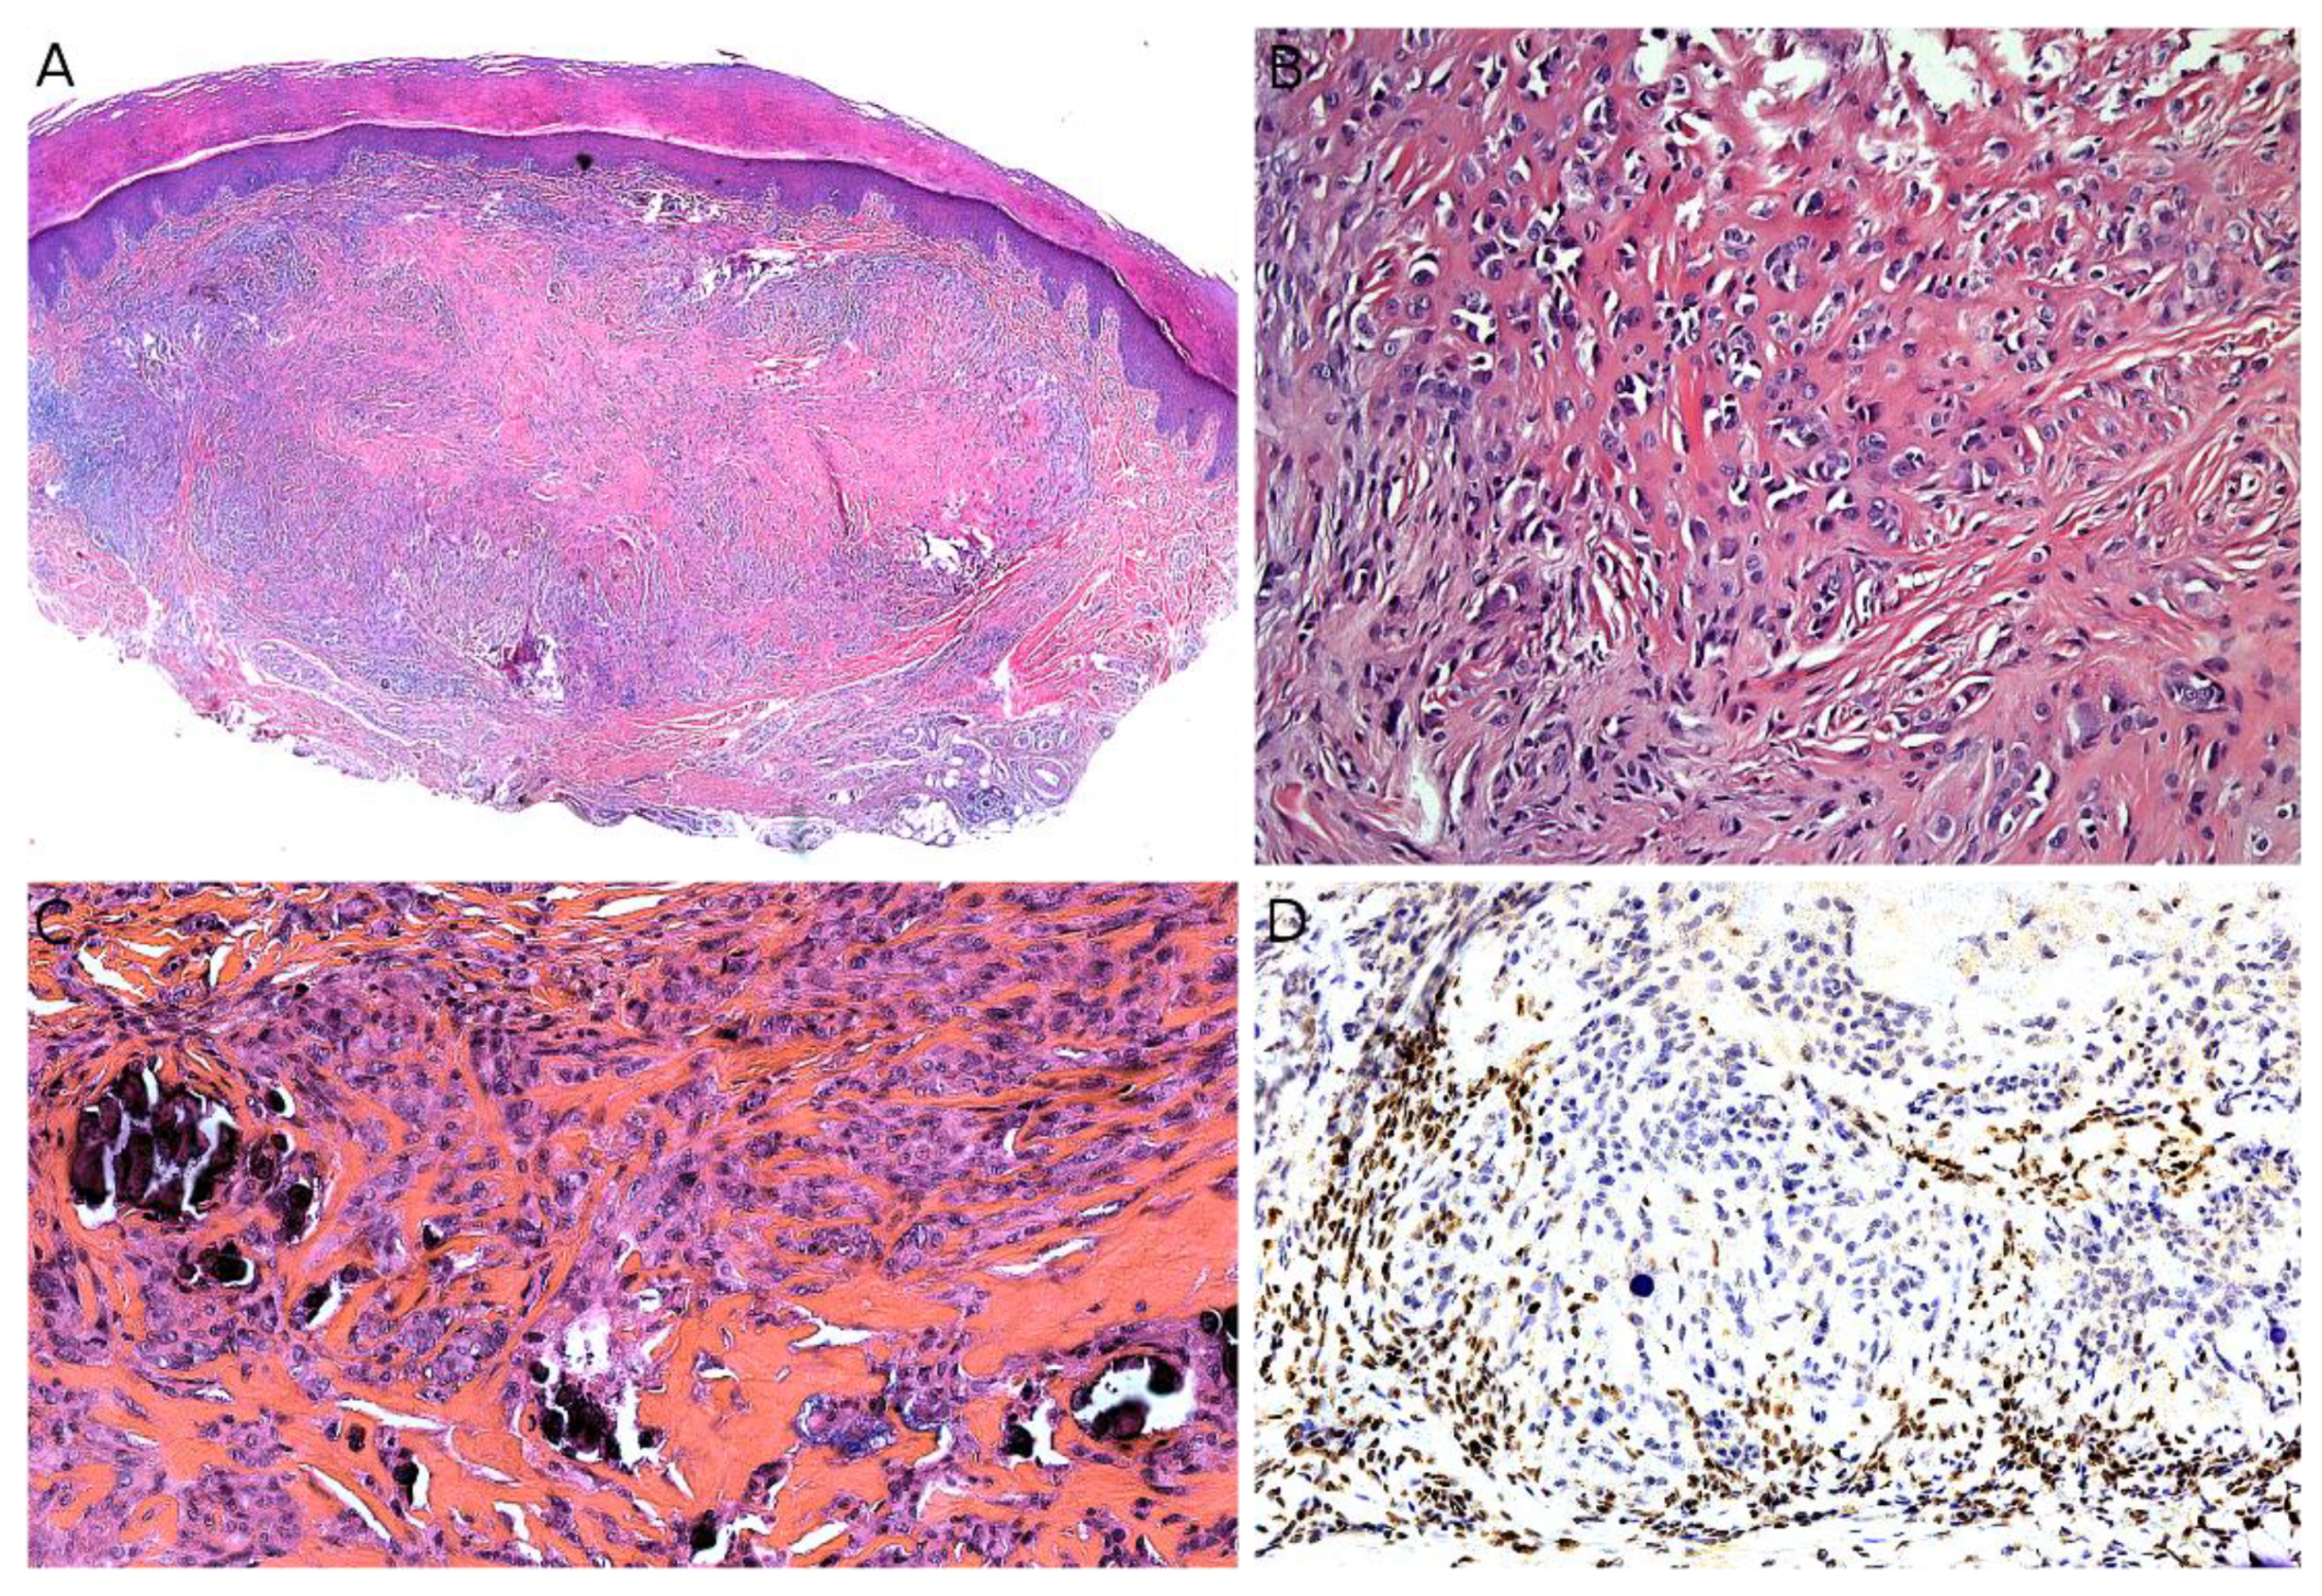

Microscopically, MPNST may adopt very diverse appearances. They often show a herringbone, fibrosarcoma-like architecture, or more haphazardly oriented fascicles. The tumor is densely cellular, with mild nuclear atypia. Mitotic activity is often elevated (Figure 14A,B). Necrosis is frequent. A divergent differentiation is possible (malignant triton tumor), such as cartilage, bone, skeletal muscle, or smooth muscle. Epithelioid MPNST represent less than 5% of all cases. Some cases are difficult to classify, with features intermediate between MPNST and cellular neurofibroma. There is currently no widely recognized recommendation for the diagnosis of such cases, termed “atypical neurofibromatosis neoplasms of uncertain biologic potential” (ANNUBP). Immunohistochemistry is useful in assessing the transformation of a neurofibroma into an MPNST. In MPNST, S100, SOX10, and H3K27me3 are often lost (Figure 14C); p16/CDKN2A is also lost (but this is also the case in some ANNUBP); TP53 may be diffusely positive in high-grade cases; and Ki67 is greater than 10% [170].

Figure 14.

Malignant peripheral nerve sheath tumor (MPNST): (A) MPNST arising on a pre-existing plexiform neurofibroma in a child with NF1, note the two highly cellular areas among the otherwise poorly cellular plexiform neurofibroma (×25); (B) higher view of one of the MPNST areas showing nuclear atypia and numerous mitoses (×100); (C) partial loss of S100 expression with only sparse positive cells (×200).